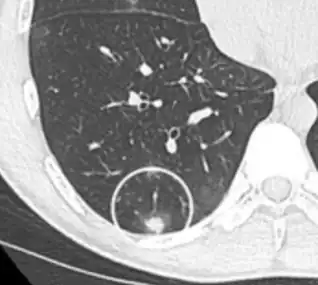

| Tomosynthesis of chronic fibrosing pulmonary aspergillosis | |

On chest X-ray and CT, pulmonary aspergillosis classically manifests as a halo sign, and later, an air crescent sign.[24] In hematologic patients with invasive aspergillosis, the galactomannan test can make the diagnosis in a noninvasive way. Galactomannan is a component of the fungal wall.[13] False-positive Aspergillus galactomannan tests have been found in patients on intravenous treatment with some antibiotics or fluids containing gluconate or citric acid such as some transfusion platelets, parenteral nutrition, or PlasmaLyte.[25][26]